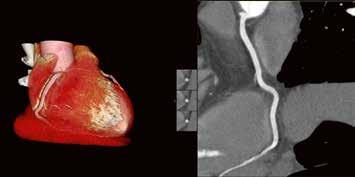

Gerade das Rauschen hat noch einmal deutlich abgenommen. In der Folge fällt die Diagnosestellung leichter. Die Begeisterung teilen viele unserer Spezialisten. So erhalten wir z. B. aus der Kardiologie die Rückmeldung, dass unsere Abteilung mit dem Hightech-CT im Vergleich zu anderen radiologischen Untersuchungen die beste Bildgebung vorweisen kann. Gerade bei Fällen, wo es um kleine Strukturen geht, Beispiel „Revaskularisierung chronischer Koronarobstruktionen“: Hier gilt unsere Bildgebung für die Planung der Rekanalisationen von chronischen Koronarverschlüssen (CTO) mittlerweile als Standard. Wir bekommen aus der Kardiologie ausschließlich Lob und eine große Zufriedenheit zurückgespiegelt. Bei der Kardiodiagnostik wird der Volumen-CT absolut priorisiert.

Die Herzuntersuchungen sind damit in unserer Abteilung auf einem Niveau angekommen, das – Stand heute – schwer zu toppen ist.

Die notwendige Dosis – schon beim zweiten Kardio-CT weniger als 1 Millisievert – ist durchgehend sehr gering. Dank der kurzen Scanzeit und der hohen zeitlichen Auflösung untersuchen wir heute selbst Herzen im Volumen-CT, bei denen wir früher gezögert hätten. So z. B. bei dem Fall

der 64-jährigen arrhythmisch Patientin mit V. a. KHK (Fall Nr. 2).

39-jähriger Pat., Z. n. venöser Stent-Anlage bei postthrombotischem Syndrom. Erbitte Gefäßdarstellung zur Stent-Revision. Aquilion PRISM (AiCE) DLP: 833,9 mGy*cm vs. 569,1 mGy*cm Aquilion PRIME (AIDR 3D)

64-jährige Patientin, Troponinämie. V. a. KHK. Frage nach KHK. 55 kg, DLP 43,9 mGy*cm, CTDI vol. 3,7 mGy.

RCA Rechter Hauptstamm Linker Hauptstamm Peripherer RIVA (AHA Seg. 8 + 10) Fall 2: RIVA RCX

76-jähriger Patient: geplante Rekanalisation bei CTO (chronic total occlusion) der RCA. Planungs-CT. CTDI vol.

3,1 mGy; DLP 37,3 mGy*cm, 80 kV, 76 – 81 BpM (763 ms), 1 Halbscan, 3 5– 5 5 %.

RCA

RIVA (wird zur Rekanalisation eingesetzt)